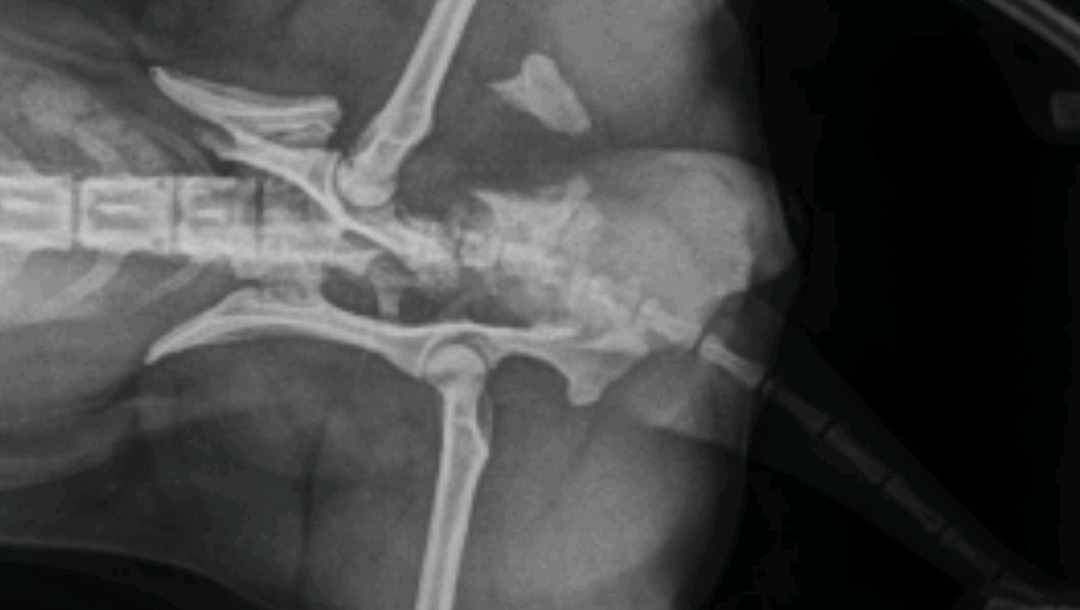

Als unser lieber Hund Maly 5 1/2 j.a. Pomeranian am 22.09.2024 ein Autounfall gehabt hat, haben die Tierärzte von Todesspritze für Maly auch gesprochen. Das könnten wir uns absolut nicht vorstellen und wollten nicht zulassen. In Folge des Unfalls erlitt Maly Beckentrümmerbruch, Schwanzabriss, innere Verletzungen, Alpträume

... Nach 21 Tagen in der Tierklinik Hofheim wurde Maly entlassen zur weiteren Behandlung ambulant und Physiotherapie. Von Monat zu Monat geht es Maly etwas besser, jedoch die Behandlungen werden noch etwas dauern. Leider war Maly damals, als der Unfall passiert nicht krank versichert. Jetzige Hundeversicherung übernimmt auch keine eventuellen weiteren Operationen, die mit diesem Unfall zusammen verbunden sein werden. Schön dass es Menschen gibt, die andere Wesen in ihrem Schicksal unterstützen. Ich gehöre auch zu diesem Kreis.